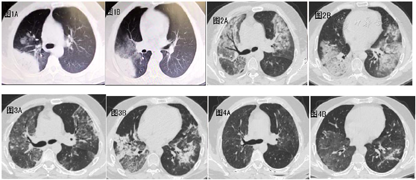

患者,男,45岁,因"反复发热、咳嗽7 d"于2019年1月16日入院。入院前7 d无明显诱因出现发热,最高体温40℃,热型为弛张热,伴畏冷、乏力,伴咳嗽,呈阵发性单声咳,偶咳少量白色黏痰,无其他不适,就诊当地卫生院予药物治疗(具体不详)后未见明显好转,仍出现反复发热,性质如前,转诊当地县医院住院,1月13号查胸部CT示"右上肺实变影"(图1A/B),予头孢他啶、氧氟沙星抗感染以及补液等治疗后,仍有发热,体温波动于38℃-39℃,伴全身酸痛、乏力,纳差、头痛,遂转入我院进一步治疗。住院期间发现血糖高,入科血糖17.3mmol/l。既往养殖鸽子二十余年,其他个人史、家族史无特殊。入科体检:呼吸急促,呼吸频率22次/分,急性面容,双肺呼吸音粗,双下肺可闻及少许湿性啰音,右侧明显,余无异常,心率67次/分,律齐,各瓣膜听诊区未闻及杂音,腹平坦,无压痛、反跳痛,腹部无包块。双下肢无浮肿。入院查血常规:白细胞计数8.22×109/L、粒细胞百分比93.1%↑、粒细胞计数7.65×109/L↑、淋巴细胞百分比4.0%↓、淋巴细胞计数0.33×109/L↓;C-反应蛋白226.0mg/L↑;降钙素原1.72ng/ml↑;血沉42.0mm/h↑;生化:葡萄糖13.75mmol/L↑、丙氨酸转氨酶239.0U/L↑、碱性磷酸酶231.0U/L↑、谷氨酰转肽酶130.00U/L↑、谷草转氨酶145.0U/L↑;凝血:D-二聚体5.56mg/L FEU↑、纤维蛋白原9.58g/L↑;糖化血红蛋白7.7%↑;尿常规:尿蛋白+↑、尿葡萄糖+↑、尿胆原++↑;过敏原:户尘螨、桑树、蟑螂、苋、芒果、腰果、菠萝、矮豚草/蒿/葎草/藜、柏榆柳栎桦枫胡桃梧桐杨阳性,总IgE 291↑;T淋巴细胞亚群:流式仪-CD3+细胞计数387个/uL↓、流式仪-CD8+细胞计数160个/uL↓、流式仪-CD4+细胞计数209个/uL↓。感染相关指标:鼻咽试纸流感胶体金检测、EB病毒DNA及IgM/IgG 、巨细胞病毒DNA及IgM/IgG 、G试验、GM试验、结核感染T细胞、结核抗体、BALF涂片找抗酸杆菌、BALF结核杆菌DNA检测、痰/BALF涂片、痰/BALF培养/呼吸道病原抗体谱、肺炎支原体血清学试验、血培养阴性;术前四项、风湿免疫指标阴性。入院考虑肺炎(双侧),具体病原菌不明。入院后因家属暂拒绝行支气管镜等有创检查,故暂予经验性厄他培南抗细菌、奥司他韦抗病毒,及复方氨林巴比妥控制体温5天,不适症状稍有改善后再次发热,体温最高40℃,咳黄脓痰,伴全身酸痛乏力、纳差、头痛,伴气喘,查体:精神倦怠、双肺闻及弥漫性湿性啰音。血气分析示PH 7.52、PCO2 33mmHg、PO2 40mmHg、FiO2 21% SO2:77%,予无创机械通气。立即复查胸部CT(1月21日)提示"两肺实变影,考虑大叶性肺炎,较前进展"(图2)。立即行床边纤维支气管镜下肺泡灌洗,选取影像学肺炎最明显的叶段(右肺上叶),吸取肺泡灌洗液行mNGS检测,同时予莫西沙星联合替加环素抗细菌,米卡芬净抗真菌联合复方磺胺甲恶唑抗PJP经验性抗感染,间断联合激素,体温稍有下降,呼吸困难缓解。1月24日mNGS结果回报为鹦鹉热衣原体,序列数225,立即调整治疗为莫西沙星400mg qd联合多西环素100mg q12h。治疗1周后复查胸部CT(1月28日)较前吸收好转(图3)。1月后复查胸部CT(2月19日)较前进一步吸收好转(图4)。

临床上,鹦鹉热衣原体肺炎可以引起全身症状,疾病无特异性,可表现为流感样症状,如头痛、肌肉酸痛、高热、呼吸困难[8,9]。感染可能导致中枢神经系统症状[10],如头晕、头痛等,可能导致肝功能异常、胃肠道功能紊乱,如呕吐、便秘和腹泻等,以及贫血等并发症[11]。病情从轻症到重症不等,在未询问或无确切鸟类接触史时,会导致误诊,治疗不及时可能导致病情加重。鹦鹉热衣原体肺炎一旦合并呼吸衰竭,提示病情危重,出现呼吸困难、紫绀、烦躁及昏迷等症状,往往预示预后不佳[12],需加强监测、尽早干预。有文献指出,甚至一些急性型病例在没有表现出任何预先征兆的情况下可出现突然死亡[13,14]。本例患者也是以流感样症状为主,一度病情好转后急转直下出现病情加重,并发呼吸衰竭,合并肝脏、神经多系统受累,符合此疾病特点。影像学方面,国外有文献显示,鹦鹉热衣原体肺炎影像表现多样化,沿胸膜下分布的结节、实变或磨玻影多见[15,16],本病例患者病灶为双肺,以右肺上叶最为严重,实质及间质均侵犯。可能与鹦鹉热衣原体毒性较强,患者免疫力较差有关。对于该病的诊断主要依靠于细胞培养、衣原体血清学、PCR或基因芯片等技术[17] ,而受病原分离培养和实验室条件等的限制,只能在专业的实验室进行,医院推广难度大。mNGS在诊断临床上罕见病原微生物中具有优势,可作为诊断鹦鹉热肺炎的一种早期、有效的方法[18]。临床上也能通过一些辅助指标,协助诊断,大部分患者外周血白细胞计数正常[19,20]。CRP高,但红细胞沉降率增快,有些肝功异常、血尿素氮/肌酐升高和低钠血症[21]。本例患者白细胞数也在正常范围内,血沉增快,谷丙谷草上升,血钠下降,与文献相符。

治疗上,由于鹦鹉热衣原体缺乏细胞壁,β内酰胺类抗生素无效。鹦鹉热衣原体肺炎治疗首选多西环素,其他有效的治疗药物包括细胞内浓度高的药物,如阿奇霉素、米诺环素、莫西沙星、左氧氟沙星等[22,23]。相关指南推荐治疗首选多西环素100毫克,q12h,疗程大于等于10天,也有推荐使用10-21天[9,24,25]。重症患者可联用四环素类和喹诺酮类[26]。本例患者我们明确诊断后使用多西环素100mg,q12h联合莫西沙星400mg,qd,治疗1周后复查胸部CT较前吸收好转。1个月后复查较前明显吸收。本例患者如家属配合能更早地行BALF送mNGS检查,将能更早明确诊断,尽早针对性治疗,防治疾病加重。